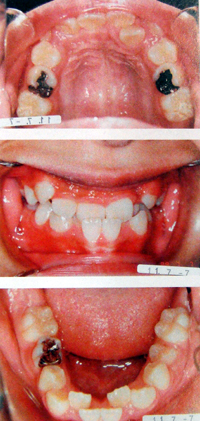

顎(あご)が小さいと、歯がきれいに並びきらないために、歯並びが悪くなりがちです。歯並びが悪いと虫歯や歯周病になりやすくなるだけではなく、いびきや無呼吸症候群になることがあります。

顎を成長させて、口の中の空間を広くし、歯並びも整えます。同時に空間が広がることにより、呼吸がしやすくなり、いびきや睡眠時無呼吸症候群を抑制することができます。

顎矯正(拡大矯正)SH療法は、1日10時間装置をはめて、あごを成長させる矯正です。お子様も大人も矯正することができます。

上記のような例で、症状が出ている場合、抜歯をせず口の中の空間を広くする装置を使用することで、症状をなくすことができます。